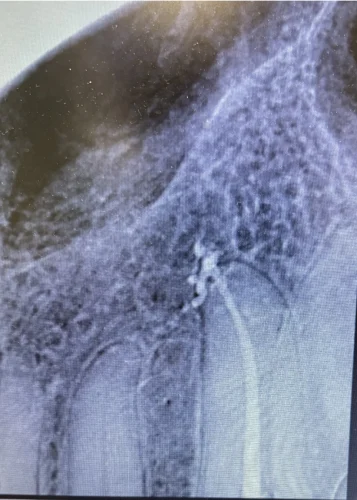

Before the procedure, all the vital signs were observed. The cleaning and shaping of canals with rotary instruments were guided by the microscope magnification during later visits. After the obturation of the canals, a digital impression was made to fabricate the crowns. The final visit consisted of cementing a zirconia crown to restore the functionality and esthetics of the teeth.

- Day 2 - completion of Biomechanical preparation of tooth #14 followed by obturation

- Day 3 - measurement of the crown ( zirconia crown preparation )

- Day 4 - cementation of crown with post delivery instructions